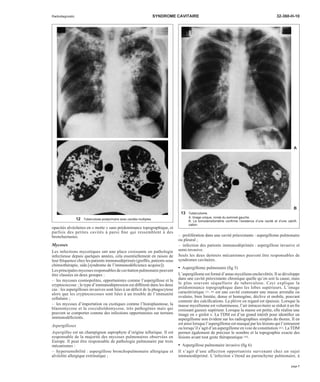

1 Tuberculose pulmonaire post-primaire.

A. Opacités hétérogènes du som-met

droit dont la cavitation est dif-ficile

à affirmer.

B. Une petite cavité est évidente

sur l’examen tomodensitomé-trique.

B